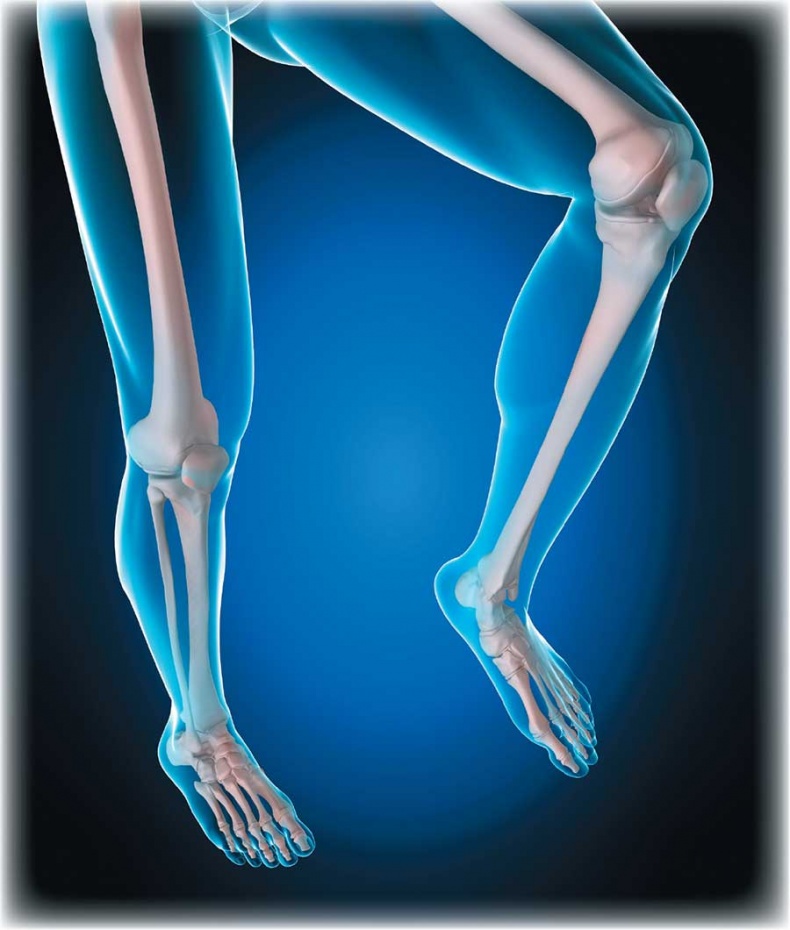

![]() Отделы позвоночника Движение позвоночника – результат работы многочисленных комбинированных суставов между позвонками. Он движется за счет действия скелетных мышц. Позвоночник способен наклоняться вперед, прогибаться (сгибание и разгибание), наклоняться вбок (отведение и приведение), а также скручиваться. Наиболее подвижны шейный и поясничный отделы. Химический состав костей взрослого человека следующий: 50 % воды, 15 % жира, 12 % органических веществ (белок, представляющий собой разновидность коллагена), 22 % неорганических веществ, а именно солей кальция в форме гидроксиапатита, и около 30 % органических веществ. Основные органические вещества кости – белки коллаген и оссеин. Сочетание волокон органического коллагена с солями кальция обеспечивает основные функции костей – прочность и упругость. Прочность – это способность противостоять внешним механическим воздействиям, упругость – возвращать первоначальную форму после окончания действия внешней силы. Минеральные вещества придают костям твердость и хрупкость, органические – гибкость и упругость. Благодаря сочетанию органических и неорганических веществ кости имеют большую прочность, что позволяет им выносить немалые нагрузки. ![]() Структура кости Соотношение органических и неорганических веществ с возрастом изменяется. В костях детей немного больше органических веществ, поэтому их кости более упругие, гибкие и реже ломаются. С возрастом в костях увеличивается доля неорганических веществ, из-за чего у пожилых людей кости менее эластичные и более хрупкие и могут ломаться даже при небольших травмах. Соединения костей связывают кости скелета в одно целое, обеспечивая им ту или иную степень подвижности. Различают три вида соединений: • непрерывные соединения, в которых полость между соединяющимися костями отсутствует, существует лишь прослойка соединительной ткани или хряща – неподвижные соединения; • переходная форма от непрерывных соединений к прерывным – симфизы, или полусуставы; имеют небольшую щель в хрящевой или соединительнотканной прослойке между сочленяющимися костями – эти образования обладают большой прочностью и очень ограниченной подвижностью; • прерывные (синовиальные) соединения или суставы; характеризуются наличием между костями полости и синовиальной оболочки, выстилающей изнутри суставную капсулу, – это подвижные соединения, а степень подвижности зависит от особенностей строения конкретного сустава. Сустав – самая распространенная и сложная форма соединения костей. Обязательными элементами любого сустава, независимо от места расположения и степени подвижности, являются суставные поверхности, суставная сумка и суставная полость. ![]() Соединение костей в коленном суставе (вверху – рентген, внизу – модель) ![]() Суставные поверхности костей, образующие сустав, плотно прилегают друг к другу. Они покрыты особым гиалиновым хрящом, чья гладкая поверхность и эластичность облегчают движение в суставе, смягчают испытываемые им толчки и сотрясения. Суставные поверхности костей окружает суставная капсула – оболочка из соединительной ткани. Обычно она крепится к костям в месте перехода суставной поверхности в надкостницу и прочно с ней срастается. Снаружи капсула укреплена связками, которые располагаются в местах наибольшей нагрузки. Суставные поверхности и капсула ограничивают собой небольшое герметично закрытое пространство – полость сустава, заполненную малым количеством вязкой синовиальной жидкости, роль которой заключается в уменьшении трения в суставах при движении. Благодаря отрицательному давлению в суставной полости поверхности костей тесно прилегают друг к другу. ![]() Суставная капсула ![]() Шаровидный сустав По форме суставных поверхностей различают плоские, цилиндрические, эллиптические и шаровидные суставы. Наименее подвижны плоские суставы, наиболее – шаровидные. Так как мы существуем в трехмерном пространстве, то в биомеханике суставов соответственно выделяют три оси вращения: фронтальную (правая – левая стороны, или наружная – внутренняя поверхности), сагиттальную (задняя – передняя поверхности) и продольную (вдоль сочленяющихся костей). В зависимости от формы суставных поверхностей в суставах может быть движение вокруг любой одной, двух или трех указанных осей (одно-, двух- и многоосные суставы). Вокруг указанных осей выполняются соответствующие виды движений. Вокруг фронтальной оси происходят сгибание и разгибание. При сгибании угол между сочленяющимися костями уменьшается (например, в локтевом суставе – угол между плечом и предплечьем). Во время разгибания движение идет в обратном направлении и происходит выпрямление (конечности или туловища). Вокруг сагиттальной оси осуществляются приведение и отведение. В случае отведения одна из сочленяющихся костей удаляется от срединной плоскости, при приведении – приближается к ней (например, отведение руки в сторону от туловища и снова приближение к нему). ![]() Наши двигательные возможности определяются прежде всего строением суставов Вокруг продольной оси кость вращается в разные стороны. Круговое движение – это последовательное перемещение вокруг всех осей, при котором свободный конец движущейся кости или конечности (например, кисти руки) описывает окружность. Размах (объем) движений в суставах зависит от многих факторов: • от разности угловых величин (выражаются в угловых градусах) сочленяющихся поверхностей (чем больше эта разность, тем больше размах движений); |